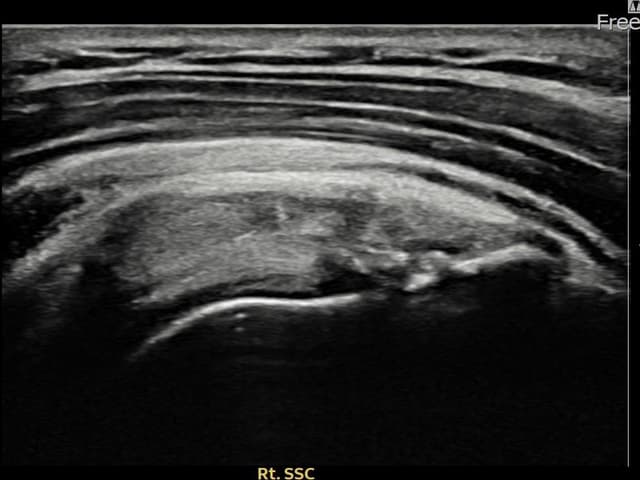

[経過期間: 24.03.21~24.05.29]

[縫縮術] 超音波検査にて右 견갑하근건 部分断裂(8mm × 3mm (腱厚の約32%欠損))を確認。縫縮術施行後、腱の連続性が回復し、日常生活に復帰されました。